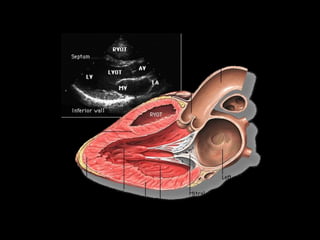

PARAESTERNAL EIXO

AL

PM